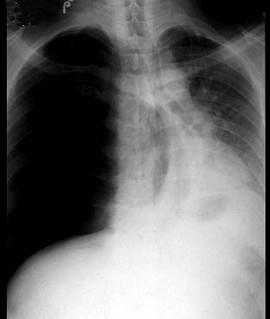

问题 男,35岁,被汽车撞伤右胸已经24小时,颜面口唇苍白,皮肤湿冷,心律120次/分,血压12/9、33kPa(90/70mmHg),呼吸困难逐渐加重,气管左移,右侧叩诊高度鼓音,右侧胸穿未抽出血液,胸部X线检查如图。最可能的诊断是 ( )

选项 A、肺内出血 B、支气管断裂 C、凝固性血胸 D、张力性气胸 E、损伤性窒息

答案 D